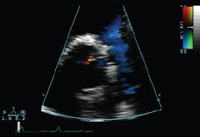

Short axis echocardiographic view in a patient with pulmonary regurgitation following repair of tetralogy of Fallot. The patient has a restrictive right ventricle, and short axis echocardiographic view reveals a small right ventricle

From: Chaturvedi RR, Redington AN. Heart. 2007 Jul;93(7):880-9; used with permission